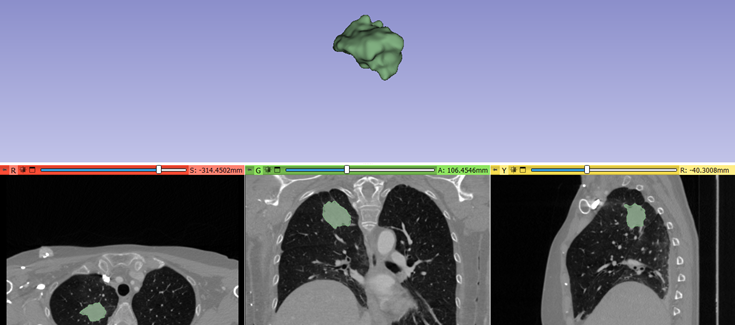

Gracias a un nuevo estudio publicado en Journal of Translational Medicine, se ha identificado un biomarcador no invasivo para predecir el beneficio clínico duradero de la inmunoterapia, basado en la integración de datos radiómicos y clínicos monitorizados, durante los primeros meses de tratamiento con anticuerpos monoclonales anti-PD-1/PD-L1, en pacientes con cáncer de pulmón no microcítico avanzado.

La inmunoterapia se ha convertido en uno de los tratamientos de referencia del cáncer de pulmón avanzado no microcítico, con tasas de respuesta prometedoras, enfermedad que sigue presentándose con una frecuencia alta. La predicción de la eficacia de la respuesta al tratamiento antes y durante el tratamiento, sigue siendo crítica para el manejo personalizado de los pacientes.